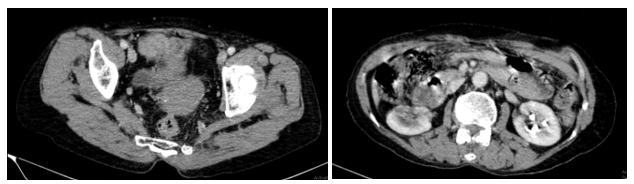

Chụp CT ổ bụng có tiêm thuốc cản quang:

Hình 1: Hình ảnh khối vùng tiểu khung kích thước 52x69mm (vòng tròn đỏ).

Hình 2: Dày lan tỏa phúc mạc, ngấm thuốc mạnh sau tiêm (mũi tên đỏ).

Hình 3: Dịch tự do ổ bụng, chỗ dày nhất 53 mm (mũi tên vàng).

Chụp CT lồng ngực:

Hình 4: Hình ảnh vài dải xẹp phổi thùy dưới phổi hai bên. Ít dịch màng phổi trái

10 mm (mũi tên đỏ).